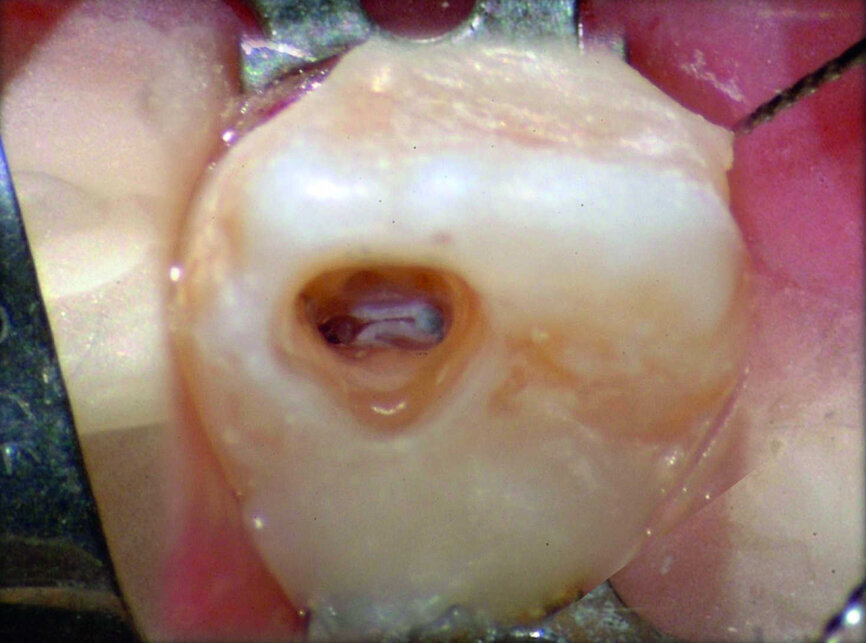

Il existe un autre avantage convaincant de cette technologie 3D : la possibilité d’utiliser une approche minimalement invasive pour préparer la cavité d’accès. À titre de démonstration, le cas suivant est celui d’une invagination amélo-dentinaire, plus connue sous le nom de dens in dente. L’examen CBCT montre une séparation entre les deux systèmes canalaires de la canine, et la carie touche la zone de la dent où se situe le dens in dente. Le plan d’intervention consiste donc en un traitement endocanalaire sur une partie précise de la pulpe, le reste du tissu pulpaire devant rester vital. La séquence d’images du traitement montre comment l’examen CBCT et un microscope chirurgical, permettent d’obtenir un accès par une préparation minimalement invasive, qui va épargner une grande partie de la couronne clinique de la canine, et préserver la vitalité de la partie non atteinte de la dent. Six ans plus tard, le suivi radiographique confirme la cicatrisation complète de la lésion, et la partie vitale de la canine ne présente aucun signe pathologique (Figs. 32–37).